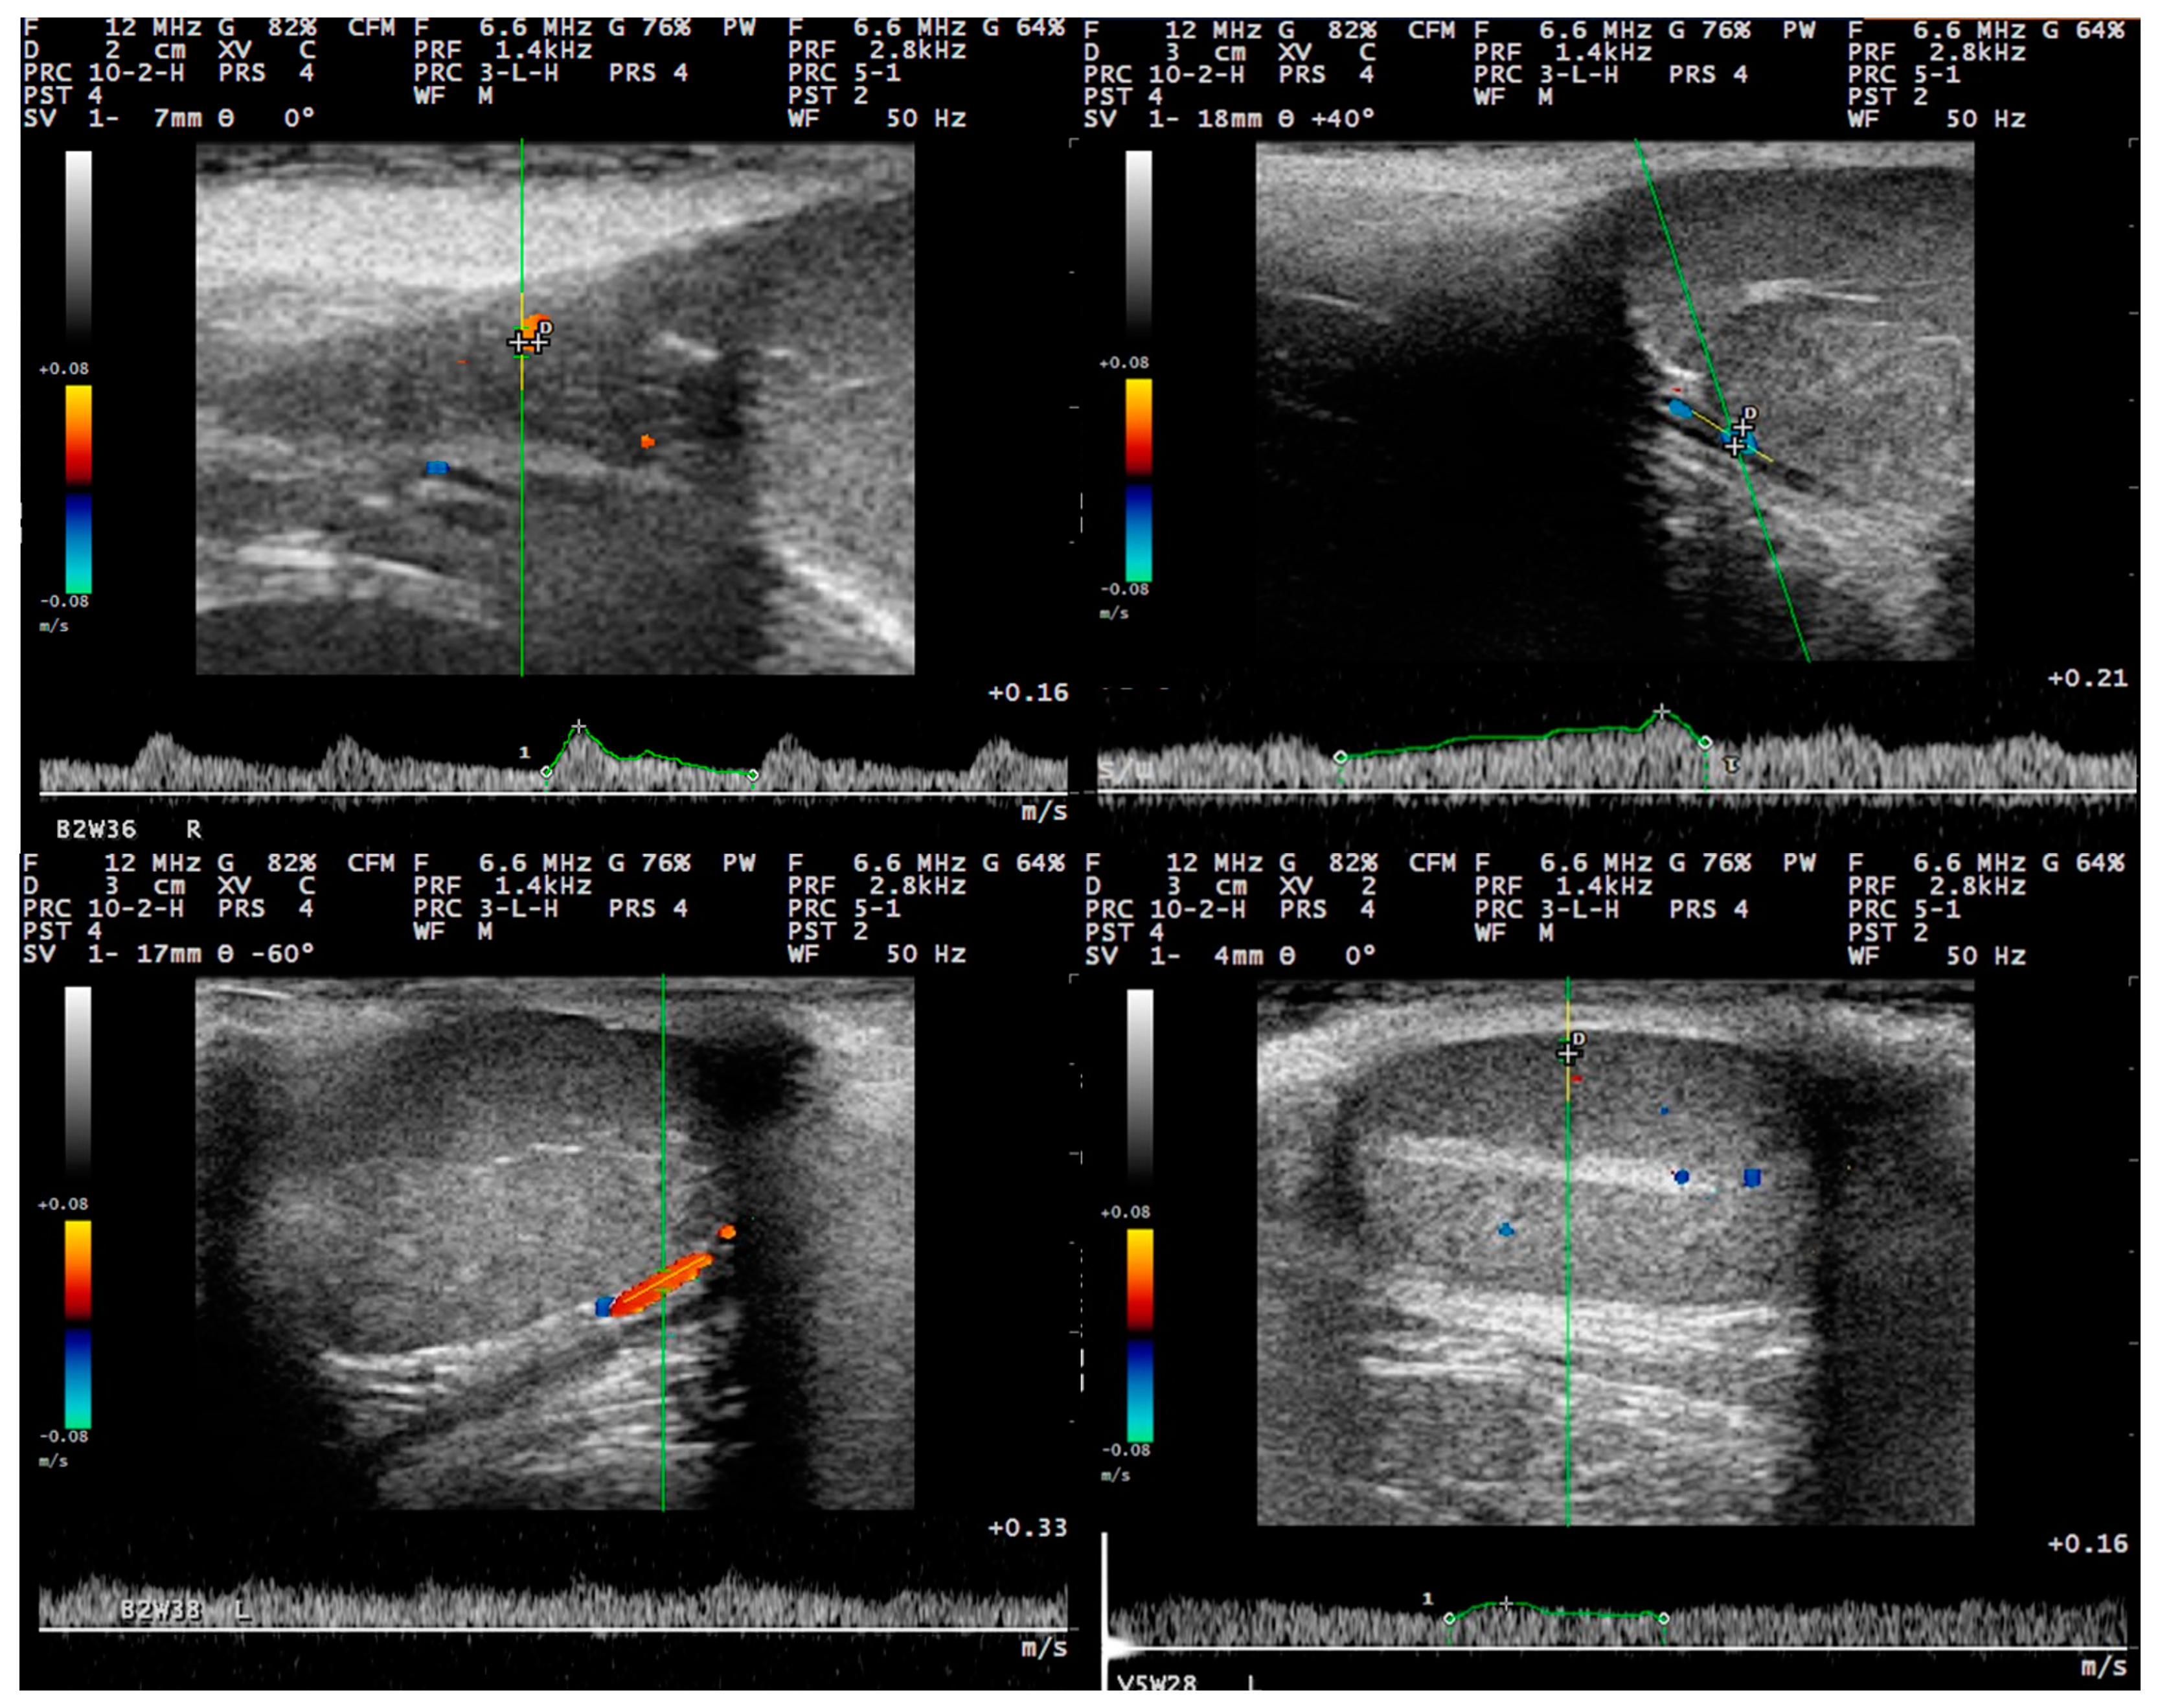

3.3. Pulsed-Wave Doppler

4.2. Differences in the Findings between the Regions of the Testis

4.4. Proposed Segments of the Artery and Haemodynamic Parameters for Doppler Evaluation